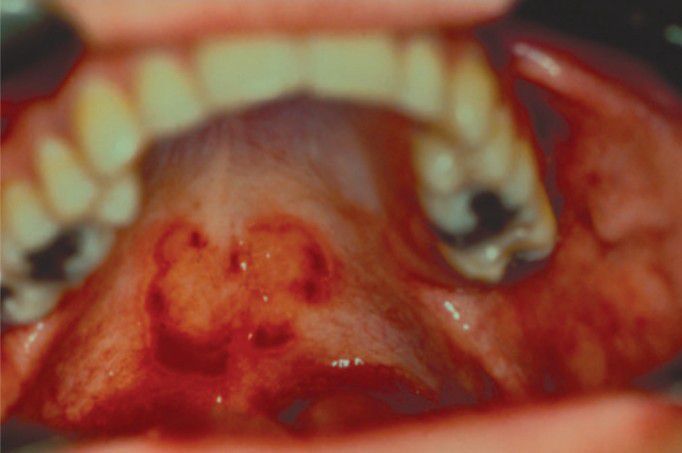

Ectopic geographic tongue

Ectopic geographic tongue involving the palate. Note the circinate configuration and strong resemblance to classic geographic tongue.